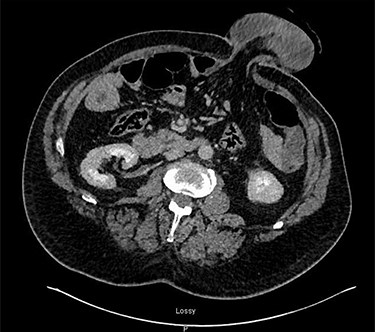

On the morning of admission, the patient’s carer noticed that he had a congested and prolapsed stoma. On presentation to the emergency department, he was hemodynamically stable. Abdominal examination revealed an ischaemic, dilated stoma site, which was prolapsed to 15 cm (Fig. 1). There was also mild tenderness on deep palpation in the supra-pubic region. His admission bloods were notable for a white cell count of 11.4, sodium of 125 and a lactate of 3.04. A CT-abdomen pelvis revealed a prolapsed, ischaemic appearing colostomy and suspicion of pneumatosis in a loop of ascending colon and the caecum was rotated in a type I volvulus to lie in the left upper quadrant (Fig. 2).